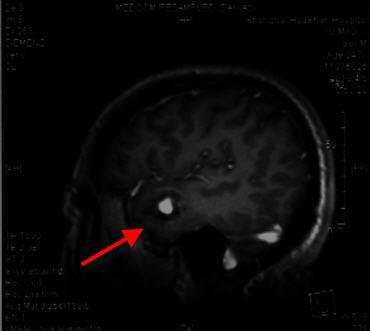

2019年2月28日头颅MRI片示:右侧颞叶见类圆形异常信号影,呈T1高信号,FLAIR周边高、中央低信号,增强后未见明显强化。

2019年4月6日头颅MRI片示:右侧颞叶见类圆形异常信号影,较前无动态变化,考虑右侧颞叶海绵状血管瘤。

4月6日头颅MRI片显示右侧颞叶见类圆形异常信号影,考虑海绵状血管瘤。